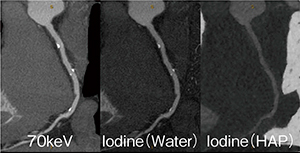

Cardiac Imagingにおいて,低エネルギーkeV画像はコントラスト差が大きくプラーク診断に有用であり,高エネルギーkeV画像はビームハードニングの影響を抑えたステント内腔の評価に有用である(図2)。同時に,両エネルギーの時間位相差のないraw dataが得られることで,“水”と“ヨード”に着目した計算から,物質の密度値や密度画像を構築することが可能である。心臓領域においては高度石灰化の近傍評価などに有用で,冠動脈石灰化の主成分とされるハイドロキシアパタイト(HAP)などの密度値をNullにしたヨード密度画像にて,石灰化からの影響を受けず内腔の診断が可能となる(図3)。この密度画像は,近年注目されるプラークの性状診断や心筋Perfusionにおいても有用性が期待されている。シングルエネルギーやCT値ベースのデュアルエネルギーではビームハードニングの影響を強く受ける下行大動脈と左室の間の領域においても,GSI Cardiacのヨード密度画像を用いることでビームハードニングによるCT値シフトの影響を受けず,精度の高い虚血診断能が期待される(図4)。

図3 モノクロマティック画像と密度画像 |